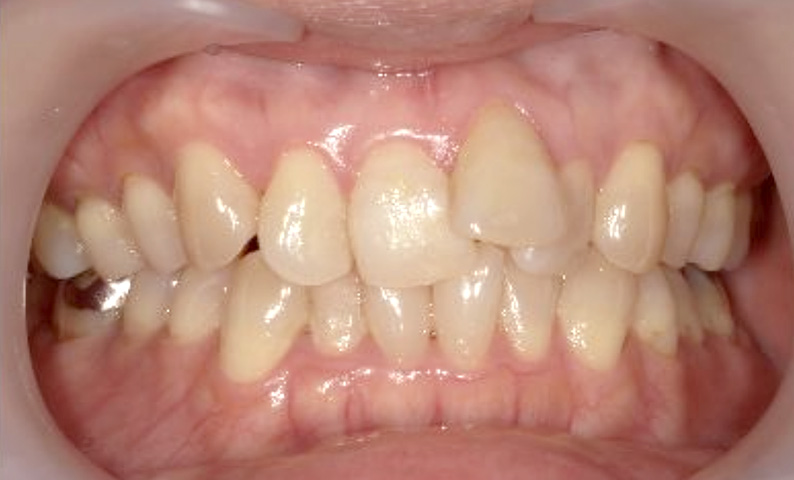

症例_003 下顎だけの部分矯正

治療期間:10ヶ月金額:24万円+税女性前歯のガタガタ下の前歯だけ上顎は補綴治療中

| Before | After |